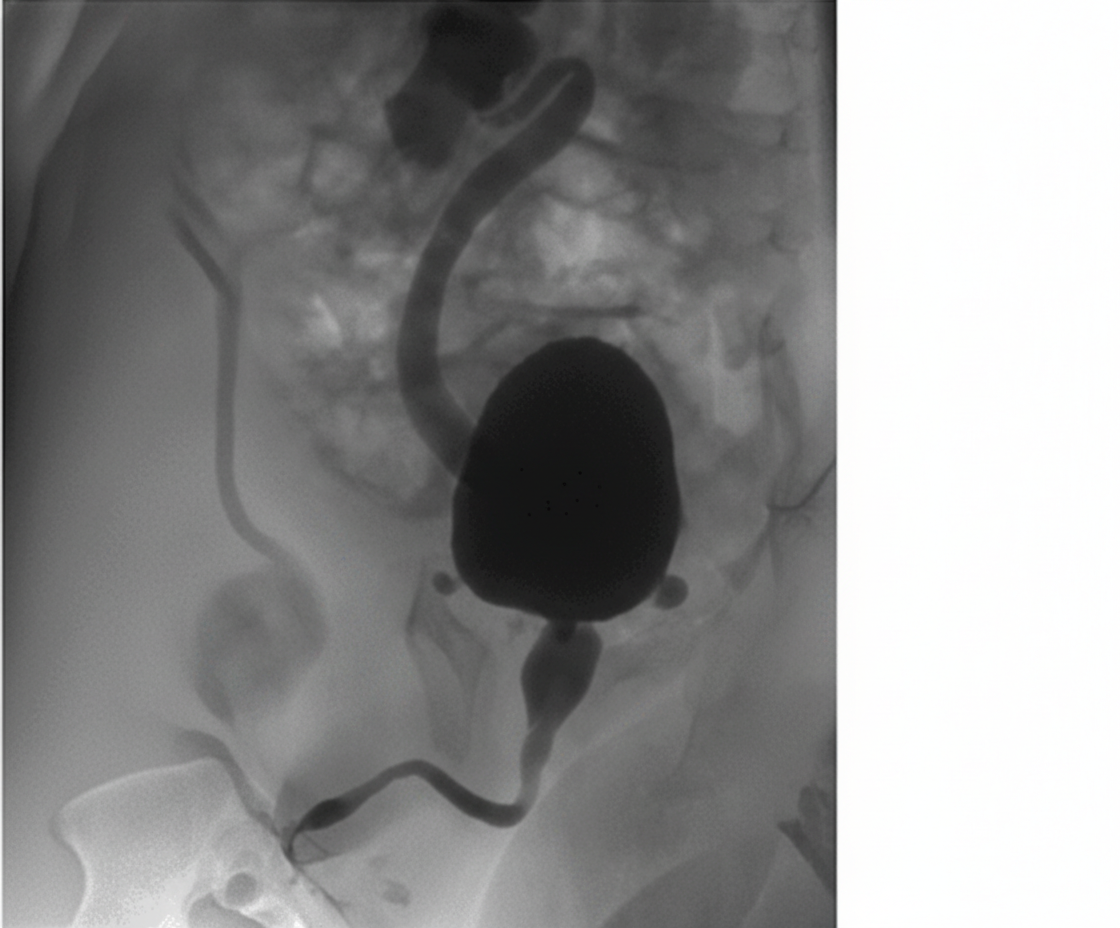

A 3-year-old child presents to the OPD with a history of recurrent urinary tract infections, poor urinary stream, and difficulty voiding. The radiological image is shown below. What is the most appropriate management?

A 2-year-old boy presents with a history of recurrent urinary tract infections, poor urinary stream, and failure to thrive. A voiding cystourethrogram (VCUG) is performed, and the images provided show dilated posterior urethra and a thickened bladder wall with a keyhole appearance. Based on these findings, the diagnosis of posterior urethral valves (PUV) is made. What is the management for this condition?

Explanation: ***Endoscopic ablation*** - The image shows a distended bladder with a dilated, elongated posterior urethra and a narrow stream of contrast beyond the bladder neck, characteristic findings of **posterior urethral valves (PUV)**. - **Endoscopic ablation (incision or fulguration)** of the valves is the definitive treatment for PUV to relieve obstruction and prevent further kidney damage. - This is the **gold standard primary treatment** for PUV in children who are large enough to undergo the procedure safely. *Dilation of urethra* - **Dilation** is generally ineffective because PUV are folds of tissue that require incision rather than simple stretching. - This approach does not address the underlying anatomical obstruction caused by the valves and could potentially cause damage to the urethra. *Dilation of urethra and bladder* - **Dilation of the urethra** is not an effective treatment for PUV. The bladder is already dilated due to the obstruction, and further dilation would not resolve the issue. - This approach would not remove the obstruction and could worsen bladder function or lead to further complications like reflux. *Conservative* - **Conservative management** with watchful waiting is not appropriate for PUV, as untreated obstruction can lead to progressive and irreversible kidney damage, bladder dysfunction, and recurrent UTIs. - Timely intervention is crucial to preserve renal function and improve long-term outcomes in boys with PUV. *Vesicostomy* - **Vesicostomy** (temporary bladder diversion) is reserved for specific scenarios such as neonates or very young infants too small for safe endoscopic ablation, severe hydronephrosis with renal failure, or failed primary ablation. - In this **3-year-old child**, endoscopic ablation is preferred as the primary definitive treatment rather than temporary diversion, which would require a second procedure later.

Explanation: ***Endoscopic valve ablation*** - This is the **definitive treatment** for posterior urethral valves (PUV) as it directly addresses the anatomical obstruction. - Ablating the valves with a **cystoscope** relieves the outflow obstruction, preventing further damage to the bladder and kidneys. *Antibiotic prophylaxis and monitoring* - While important for managing recurrent UTIs and preventing future infections in children with PUV, it does **not address the underlying anatomical obstruction**. - Without surgical intervention, the obstruction would persist, leading to progressive urinary tract damage despite antibiotic use. *Suprapubic cystostomy* - This procedure involves placing a catheter directly into the bladder via the abdominal wall to **divert urine**. - It is typically a **temporary measure** used for initial decompression in severely ill patients or those with complete obstruction, not the definitive management. *Urinary diversion with vesicostomy* - Vesicostomy creates an opening between the bladder and abdominal wall for temporary urinary diversion. - This may be used in **very young infants** or critically ill patients as a temporizing measure, but **endoscopic ablation remains the definitive treatment**. *Observation with follow-up imaging* - **Observation is not appropriate** for symptomatic PUV due to the risk of progressive and irreversible renal damage. - The condition requires **prompt intervention** to relieve the obstruction and prevent long-term complications like renal failure.